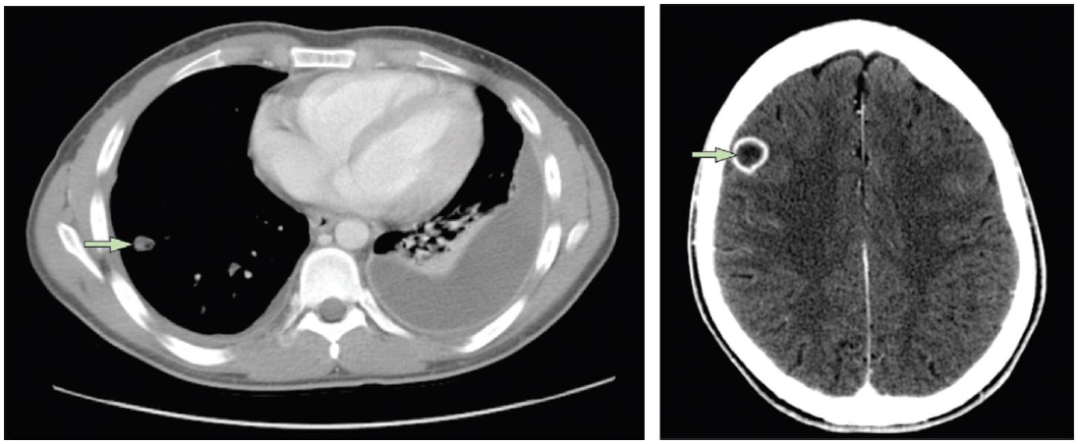

Lancet Infect Dis上发表的一篇文献报道了一例18岁男性患者,咽痛、发热,未引起重视,4天后咽痛仍加剧 → 诊断“扁桃体炎” → 2天后因扁桃体炎及肺炎收入院 → 左脸及颈部肿胀 → 颈内静脉血栓性静脉炎,血培养发现坏死梭杆菌 → 后续影像学发现肺脓肿、右额叶脑脓肿。该患者的治疗疗程持续约半年后病情才得以好转。

图片

图片来源:Lancet Infect Dis, 2012,12(10):808-815.

我院23岁男性患者,化脓性扁桃体炎+颈静脉血栓+肺脓肿,抗感染治疗2月余,病灶逐渐消失。